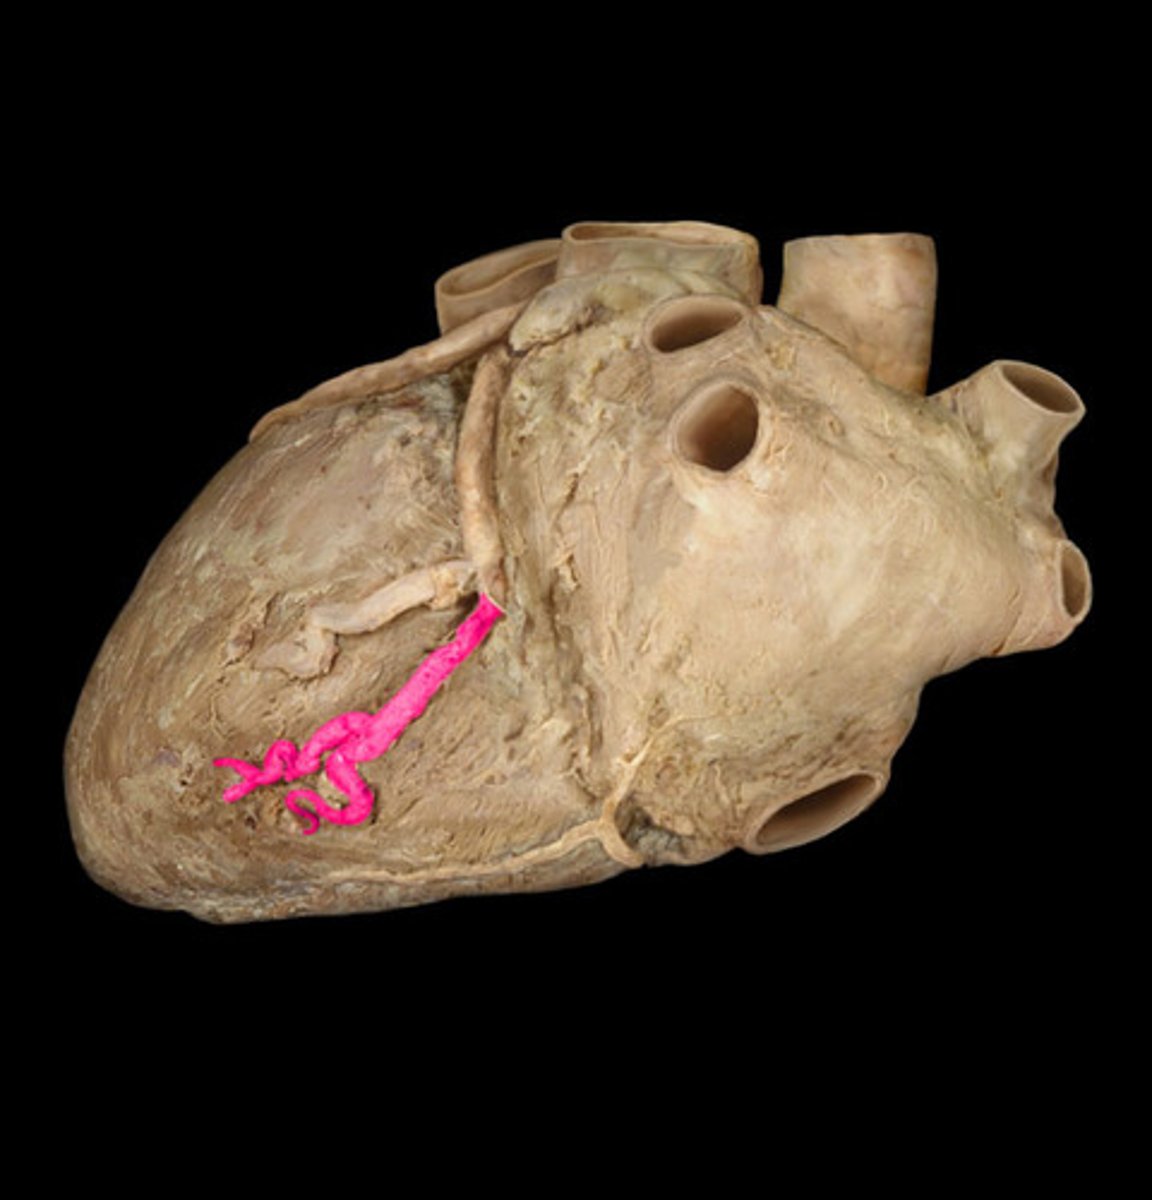

circumflex artery

bends around the heart

left side, looks like ramen noodles

coronary sinus

largest vein of the heart, in the posterior coronary sulcus

middle of the 'T'

great cardiac vein

begins in the anterior interventricular sulcus

left side of the 'T'

middle cardiac vein

posterior interventricular sulcus

middle string coming out of sinus